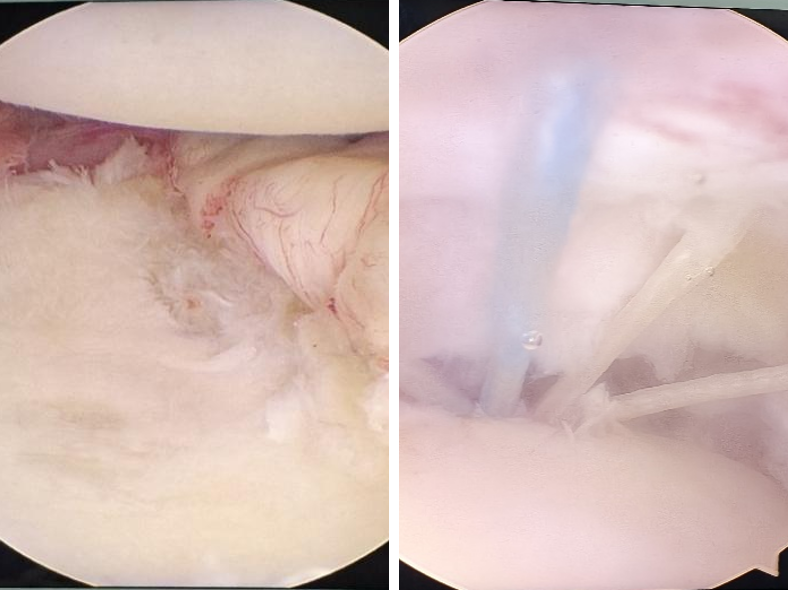

术中探查关节情况

关节镜下修补固定肩关节盂

关节镜下固定大结节骨块及修补肩袖